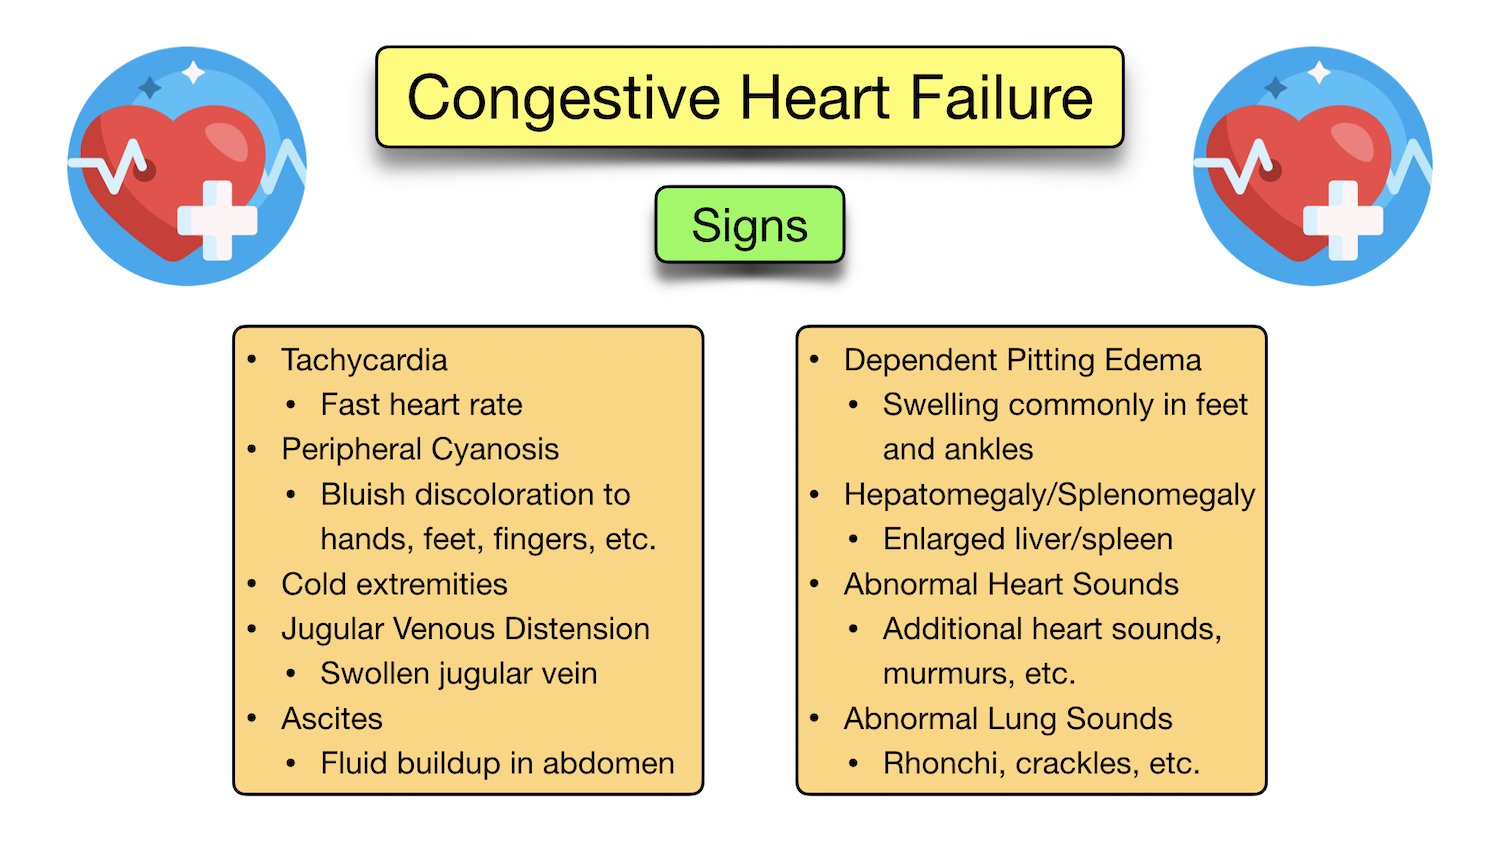

Congestive Heart Failure Symptoms